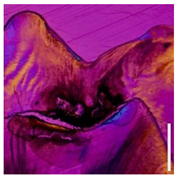

Classification and statistical analysis: Using custom MATLAB® (MathWorks, Natick, MA, USA) code, a graphical user interface (GUI) for reading, visualizing and selecting hyperspectral data was developed. Within this GUI, ten data points in close proximity to the histologically validated region were selected manually for each tooth (Figure 2a). The corresponding reflectance spectra were saved for further processing and associated with the histological occlusal state by binarization (0 = stained, 1 = stained lesion). The number of teeth and spectra within each occlusal health state group is shown in Table 1. In order to remove potential noise from the spectra, an additional second dataset was generated by applying a Savitzky–Golay filter (order = 2, frame length = 7) to the selected raw reflectance spectra (Figure 2b). The Savitzky–Golay filter is well established in (hyper)spectral data analysis because it enables an increase in data precision without distorting the underlying signal [30]. Intensities at the wavelengths 505–525 nm were eliminated due to the high noise level of the camera sensor in this region.

Figure 2.

(a) HSI spectra were selected (white crosses) within the central fissure near the histological cross-sectional plane (dashed line) and (b) preprocessed, including (i) the elimination of wavelengths with high noise (505–525 nm; shaded red) and (ii) filtering of spectra to find the optimal data configuration for classifier training.